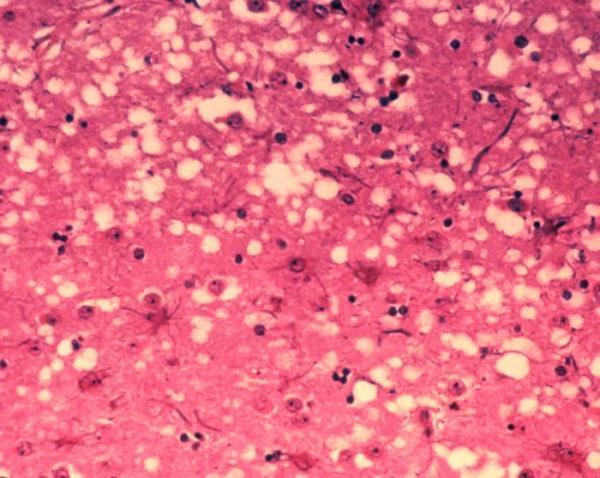

BSE causes degenerative changes in the patient’s brain, characterized by vacuole formation (http://www.sciencedaily.com)

The disease, commonly known as Mad Cow, is caused by abnormal molecules called prions that, once ingested, travel to the animals’ brains causing degenerative changes leading to neurologic signs such as tremors, incoordination or seizures. The disease is not infectious and does not transmit from a live animal to another animal. However, transmission can occur through ingestion of parts of affected animal that contain the prion, such as the brain or spinal cord tissue. This is why BSE has traditionally been associated with a practice consisting of feeding beef-based diets to cows, in order to promote protein intake. This practice is, however, illegal now in most countries, including the US and that has led to a decrease in BSE worldwide.